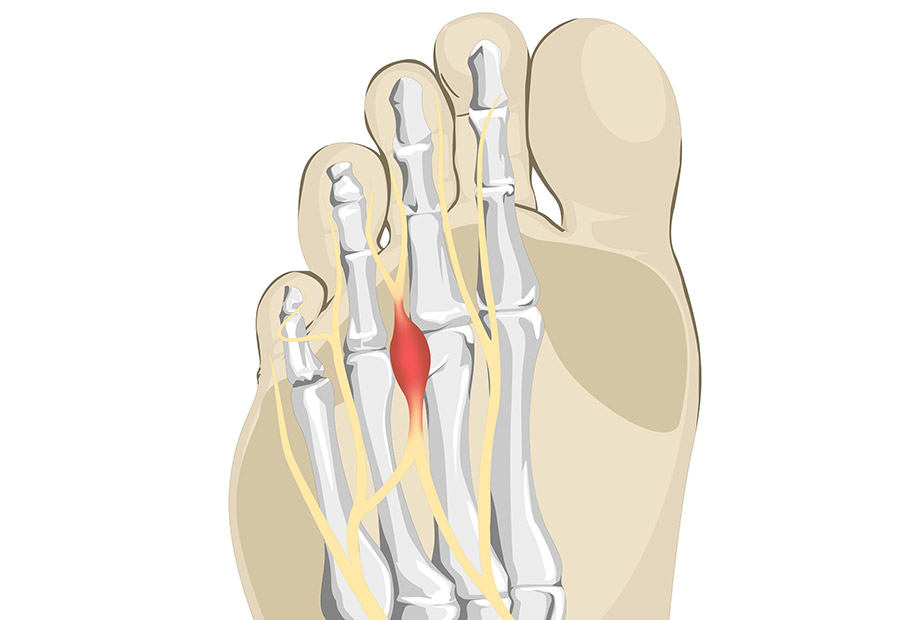

Morton’s neuroma

Description:

This is the term used to describe an inflamed nerve that runs between the toes and when pinched between bones causes pain when walking, usually described as if “walking on a pebble”.

Treatment:

Non-operative treatment is the norm with footwear modification, insoles and an injection. Surgery is rare but indicated in severe cases.